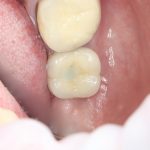

Рекомендации по установке имплантов. Для всех. Часть V.